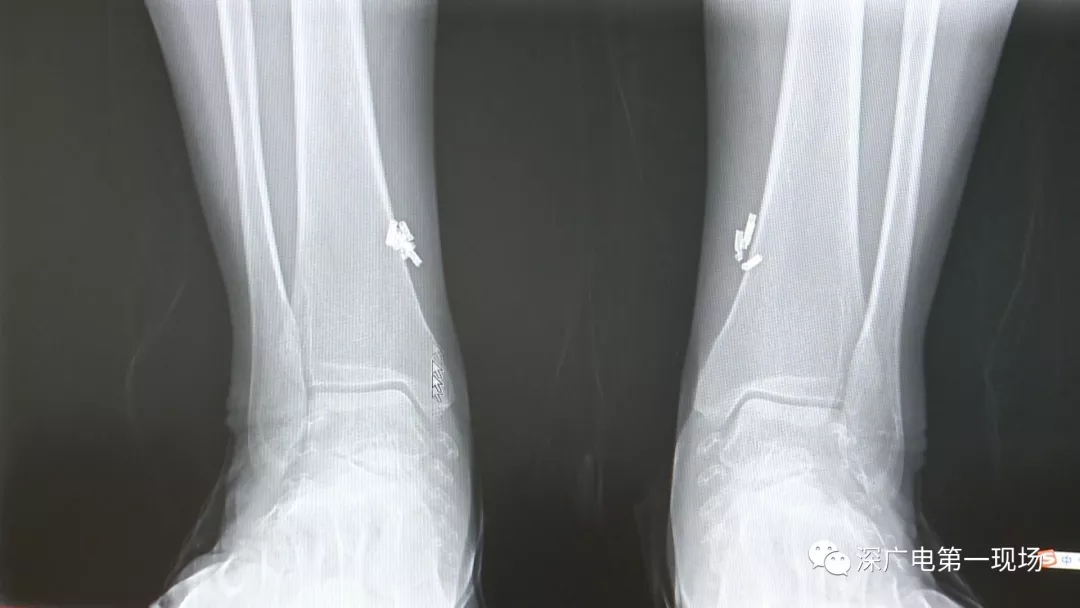

從X光影像圖片中可以看到

患者周身布滿(mǎn)了彈簧圈

深圳大學(xué)總醫(yī)院神經(jīng)外科副主任醫(yī)師陳富勇介紹,當(dāng)時(shí)檢查的時(shí)候發(fā)現(xiàn),該患者從頭部到腿部,基本上每個(gè)地方都有彈簧,很難數(shù)清具體數(shù)目。